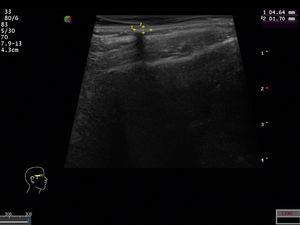

La aportación al diagnóstico preoperatorio de la ecografía de partes blandas cada vez es más notable. La serie de Solivetti et al. recoge un total de 124 pilomatricomas, de los que un 25,8% tienen hecha ecografía previa. El tumor se ve como un nódulo hiperecoico o isoecoico con refuerzo periférico y sombra posterior, diferenciando hasta 5 patrones ecográficos característicos del pilomatricoma11, por lo que reconocen la ecografía como una prueba importante para el diagnóstico preoperatorio. En nuestra serie se realizó ecografía de partes blandas al 21,84% de las lesiones, y se encontraron imágenes compatibles con pilomatricoma en 48 de las mismas —un 84,21% del total de lesiones estudiadas— mientras que resultó inespecífica o no compatible en 9 casos; esto puede estar en relación con la experiencia del médico y la heterogeneidad de criterios, al no estar todas las ecografías realizadas e informadas por el mismo radiólogo.

De los 239 pacientes recogidos 120 eran mujeres (50,21%) y 119 varones (49,79%). La edad al diagnóstico osciló entre 1 y 83 años, con una media de 26,4 años. Un 46,03% de los pacientes tenía una edad igual o inferior a 16 años. La localización más frecuente de las lesiones fue la cabeza y el cuello (49,81% de casos), seguida de las extremidades superiores (24,52%), el tronco (15,32%) y las extremidades inferiores (9,58%) (tabla 1). La forma clínica de presentación más frecuente fue como un nódulo subcutáneo firme, que era asintomático en el 82% de los casos (fig. 1). El diagnóstico clínico preoperatorio fue de pilomatricoma en el 54,4% de los casos; el siguiente diagnóstico clínico más frecuente fue el quiste epidérmico (26,44%). Se consideraron otros muchos diagnósticos clínicos, tanto benignos como malignos, cuya especificación y número de casos quedan recogidos en la tabla 2. Cincuenta y nueve de los 239 pacientes tenían otras enfermedades que se recogen a continuación: otras dermatosis en 16 pacientes (múltiples nevus melanocíticos y lesiones pigmentadas en seguimiento en 5 pacientes, acné en 2 casos, carcinoma basocelular en 2 casos, psoriasis, acantosis nigricans, liquen plano, liquen escleroso genital, lipomatosis múltiple, nevus sebáceo y verrugas vulgares múltiples); tumores malignos en 10 pacientes (cáncer de mama en 2 casos, melanoma, feocromocitoma, cáncer de colon, endometrio, cérvix, próstata, páncreas e hígado); enfermedad cardiovascular en 9 pacientes (cardiopatía isquémica, insuficiencia venosa crónica, estenosis aórtica, arteritis de la temporal, hipertensión arterial y diabetes), trastornos endocrinológicos en 7 casos (hipotiroidismo, talla baja, obesidad mórbida, síndrome del ovario poliquístico, pubarquia precoz, síndrome de sobrecrecimiento e hiperandrogenismo), enfermedad respiratoria en 6 pacientes (asma, síndrome de apnea obstructiva del sueño o enfermedad pulmonar obstructiva crónica), enfermedad de Steinert en 3 pacientes, enfermedades del aparato digestivo en 2 pacientes (hepatopatía y enfermedad celiaca), trastorno de déficit de atención con hiperactividad en 2 pacientes y casos aislados de síncopes vasovagales, migrañas, artrosis y quistes renales (tabla 3). Siete pacientes recordaban un traumatismo previo en el lugar de aparición del tumor, en concreto 2 de ellos referían traumatismo con la punta de un lapicero, uno picadura y uno vacunación previa. Se registraron 20 casos de pilomatricomas múltiples (8,39% de los casos): un paciente con 4 pilomatricomas, 4 pacientes con 3 pilomatricomas y 15 pacientes con 2 pilomatricomas cada uno; el único paciente que presentaba 4 pilomatricomas se encontraba en estudio por un síndrome de sobrecrecimiento y además tenía una hermana a la cual también se le extirpó un pilomatricoma. Otros 2 de los casos múltiples correspondían a pacientes con enfermedad de Steinert ya conocida (fig. 2) y uno tenía un carcinoma de endometrio como enfermedades asociadas. Tres de los pacientes a los que se les extirpó un pilomatricoma en nuestro hospital aportaban informe anatomopatológico de un pilomatricoma previo extirpado en otro centro y en otra localización. Se realizó ecografía de partes blandas a 57 de las 261 lesiones (21,84%), la cual presentó imágenes compatibles con pilomatricoma en 48 casos (fig. 3) y resultó inespecífica o no compatible en 9 casos. Desde el punto de vista histológico la gran mayoría de los casos presentaban las características propias de los pilomatricomas previamente descritas (fig. 4); se registraron 5 quistes híbridos (quiste epidérmico y pilomatricoma en la misma pieza), un caso de pilomatricoma anetodérmico, que fue diagnosticado preoperatoriamente, un caso de osificación, un pilomatricoma con queratosis seborreica acantósica y un quiste folicular con áreas de tipo tricolemal-epidérmico y pilomatricoma. No ha habido ningún caso de carcinoma pilomatrical, ni áreas de malignización en ninguna de las lesiones.